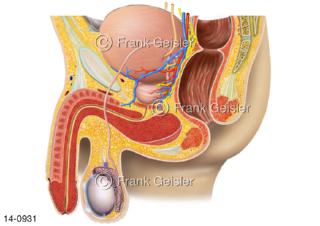

Bildergalerie Urogenitalsystem

Bilder zum Urogenitalsystem mit Urogenitalorgane, Urogenitaltrakt, zum Harn- und Geschlechtsapparat, Harnorgane und Geschlechtsorgane, Organe der Harnwege und der Fortpflanzung, Harnorgane und Geschlechtsorgane im männlichen und weiblichen Urogenitalsystem